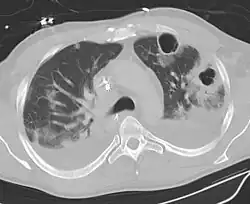

Computed tomography (CT) scan of chest showing bilateral pneumonia with abscesses, effusions, and caverns. 37-year-old male.